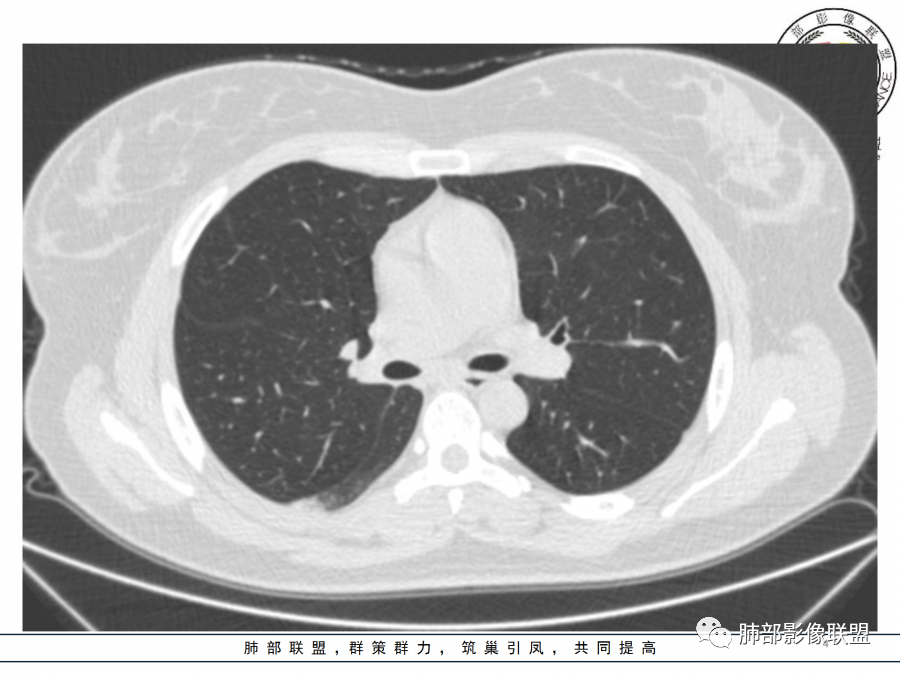

右肺胸膜下实变,病变跨多个叶生长,宽基底与胸膜相连,近端支气管穿行病灶内,并可见片状磨玻璃影,边界清,部分远端小支气管堵塞,支气管略有扩张,周围散发小结节,临床年轻女性,炎性指标高,发热六日,首先考虑感染性病变(肺链,奴卡,隐球,OP)鉴别淋巴瘤。

年轻女性,无明显诱因发热,体温略高,起病较急,有畏寒,右下肺紧贴胸膜下片状实变影,部分融合,外围有结节影,性质比较单一,类似于蘑菇兄弟,病灶周围伴有晕,支气管进入近端扩张远端堵塞,常规考虑感染,肺炎链球菌、隐球菌。

青年女性,发热咳嗽5天,炎症标志物升高。右肺下叶大片实变伴周围GGO,GGO内未见细网格,主体与胸膜平行,似多个病灶融合,实变区内见支气管部分进入,部分支气管受压狭窄,周围可见多发卫星病灶。支持炎性,考虑隐球感染,鉴别op。

年轻女性,急性起病,咳嗽,发热,黄痰,白细胞高,CRP基本正常,基础体健。CT提示右肺下叶实变,宽基底与胸膜相连,长轴平行于胸膜,可见支气管充气征,于病变中央截断,走形自然,胸膜下脂肪间隙可见,倾向于隐球菌,鉴别肺链,军团菌等。

年轻患者,右肺下叶大片状实变影,长轴与胸膜平行,内见含气支气管征,周围磨玻璃晕影。考虑感染性病变,隐球?

病灶长轴与胸膜平行,边缘有晕,病灶融合趋势,支气管进入,走行自如,考虑隐球菌肺炎。

年轻女性,急性发病,咳嗽咳痰五天,炎性指标升高,右肺下叶胸膜下大片实变影,周围见磨玻璃影,边界清晰,长轴与胸膜平行,呈融合趋势,支气管进入走行自然,远端截断,考虑炎性,隐球菌可能。

年轻女性,发热,急性发病,白细胞高,右肺下叶大片实变,长轴与胸膜平行,内见支气管走行,远端截断,周围有晕,晕边界清,考虑感染,隐球可能,鉴别淋巴瘤。

年轻女性,右肺下叶胸膜下多发实变、结节影,宽基底与胸膜相连,边缘模糊不清,实变内见支气管穿行,血象高,考虑感染性病变,大叶性肺炎?隐球?

青年女性,发热咳嗽急性起病,右肺下叶大片状实变密度影,长轴平行于胸膜,边缘模糊可见磨玻璃影及高密度结节影,实变内可见支气管穿行,直达病灶远端,考虑感染性病变,隐球菌可能大。

右肺胸膜下实变,病变跨多个叶生长,相互融合,宽基底与胸膜相连,支气管气象,并可见片状磨玻璃影,边界清,炎性指标高,发热六日,考虑感染病变,链球菌?腺病毒待排。

右肺下叶大片状实变影,长轴平行于胸膜,边缘模糊可见磨玻璃影,支气管进入,部分近端阻塞,考虑感染性病变,隐球菌,鉴别大叶性肺炎。

年轻女性,起病急,白细胞,C反高,存在感染。右下肺大片实变影,支气管充气征,长轴平行胸膜,似多个病灶融合,周围GGO,部分清,部分不清。考虑感染,隐球可能。

青年人,右肺多发团片状阴影,边缘模糊,周围可见磨玻璃影,内部有支气管空气征,考虑感染性病变,隐球菌感染可能。

右肺下叶大片状实变影,从外向内,长轴平行于胸膜,边缘模糊,可见磨玻璃影,支气管进入,远端部分阻塞,考虑感染性病变,隐球菌,鉴别淋巴瘤。

26岁,女性,发热、咳嗽5天。咳少量黄痰,起病急,病程短,白细胞及中性高,血沉及D-二聚体增高。胸部CT:右肺下叶大片实变,长轴沿胸膜分布,宽基底与胸膜接触,边界不清,周围GGO,部分团片影融合,病灶内可见支气管充气征,部分支气管进入病灶后阻塞。考虑:感染性病变,隐球菌?脓毒肺栓塞?鉴别:肺炎型肺Ca。

年轻女性,右肺下叶一大片实变影,似有多个结节影融合,周围有晕,内见支气管充气征,部分支气管进入后截断,病变近胸膜,长轴胸膜平行,考虑炎性,隐球菌首先考虑。

青年女性,影像表现右肺下叶胸膜下大片状实变影,近端见充气支气管征,边缘见片状磨玻璃影,下叶背段尚可见一结节。考虑感染性病变,隐球菌感染可能。

右下肺大片实变影,空气支气管征,边缘GGO,小叶间隔增厚,周围有蘑菇兄弟,基底宽,与胸膜平行,考虑隐球菌感染,鉴别肺炎型肺癌。

晨读:年轻女性,右肺胸膜下实变影,平行于胸膜,边缘磨玻璃影,内见支气管充气征,走形自然,略扩张。考虑感染性改变,隐球,肺链。2月发病,病毒性肺炎要考虑。鉴别淋巴瘤。

晨读:年轻女性,发热咳嗽5天。白细胞计数升高。右肺下叶大片状高密度影,边缘模糊,有实变 GGO,其内见支气管气相、无受压变细,无枯枝表现,其近端支气管无异常,右肺下叶背段见结节状影,定性考虑:炎症,隐球菌感染可能,炎症型肺癌不支持。

右下肺胸膜下大片状高密度影,其长轴与胸膜平行,病灶近端GGO模糊,部分支气管进入后阻断,支持感染性病变,考虑隐球菌